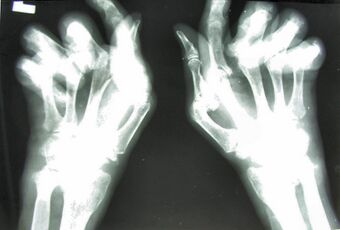

Arthritis mutilans is a rare medical condition involving severe inflammation damaging the joints of the hands and feet, and resulting in deformation and problems with moving the affected areas; it can also affect the spine.[1] As an uncommon arthropathy, arthritis mutilans was originally described as affecting the hands, feet, fingers, and/or toes, but can refer in general to severe derangement of any joint damaged by arthropathy.[2] First described in modern medical literature by Marie and Leri in 1913, in the hands, arthritis mutilans is also known as opera glass hand (la main en lorgnette in French), or chronic absorptive arthritis.[3][4] Sometimes there is foot involvement in which toes shorten and on which painful calluses develop in a condition known as opera glass foot, or pied en lorgnette.[5][6]

For a person with arthritis mutilans in the hands, the fingers become shortened by arthritis, and the shortening may become severe enough that the hand looks paw-like, with the first deformity occurring at the interphalangeal and metacarpophalangeal joints. The excess skin from the shortening of the phalanx bones becomes folded transversely, as if retracted into one another like opera glasses, hence the description la main en lorgnette. As the condition worsens, luxation, phalangeal and metacarpal bone absorption, and skeletal architecture loss in the fingers occurs.[5]